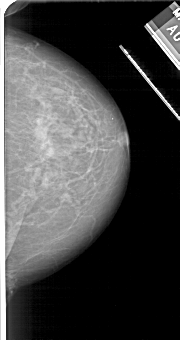

A_1112_1.LEFT_MLO

LEFT_MLO LINES 5116 PIXELS_PER_LINE 2731 BITS_PER_PIXEL 12 RESOLUTION 43.5 OVERLAY